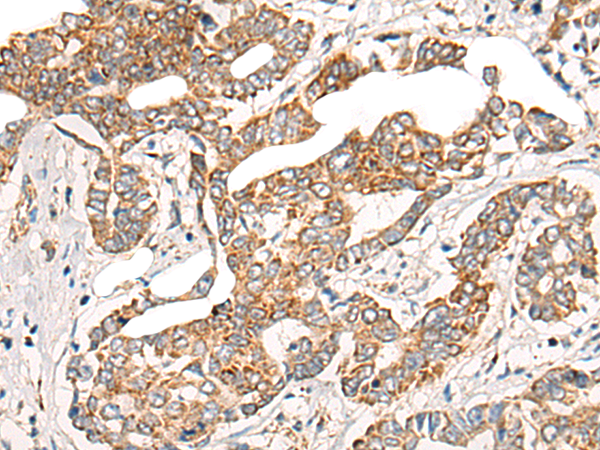

IHC positive control: |

Human thyroid cancer and Human liver cancer |

IHC Recommend dilution: |

25-100 |